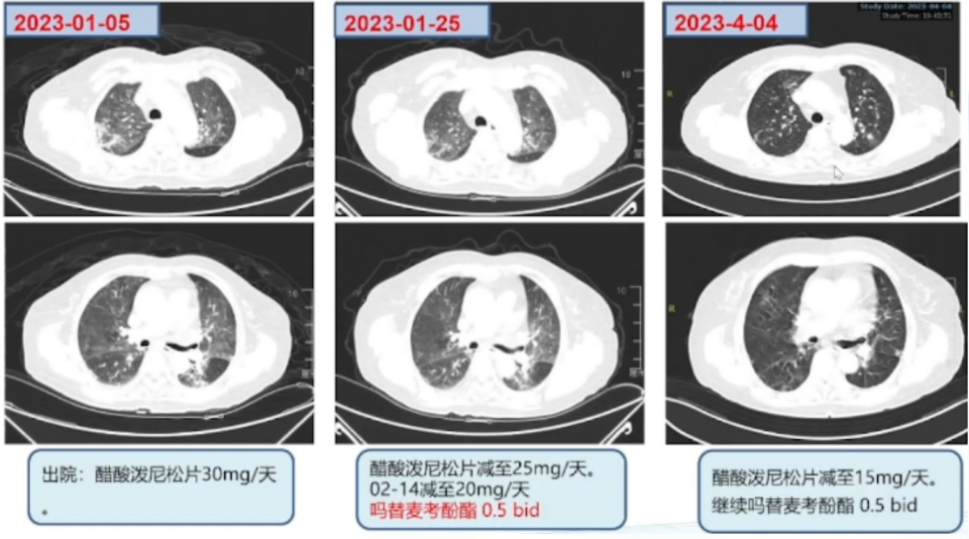

调整治疗1周后(2023-01-04)复查床旁胸片:两肺渗出较前有所吸收(图4)。复查胸部CT(2023-01-05): 两肺的磨玻璃影和渗出影较外院片显著吸收, 病变范围明显缩小(图5)

图片

5  治疗前后胸部CT对比

患者出院2周门诊复诊,气喘减轻,血常规、生化均未见明显异常。胸部CT:两肺磨玻璃影较前明显吸收(图6)

6  随访胸部CT